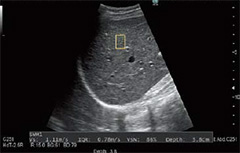

・eFocusing

eFocusingは,新しく開発した送受信技術です。S/Nの改善とフォーカス依存性の低減を実現しました。被検者依存が少なく,浅部から深部まで均一な画像を得ることができます。

・Carving Imaging

組織構造の視認性の良さを追求した,画像処理パラメーターです。

ノイズレスでクリアな画像を提供することが可能になり,診断のしやすさに貢献します。